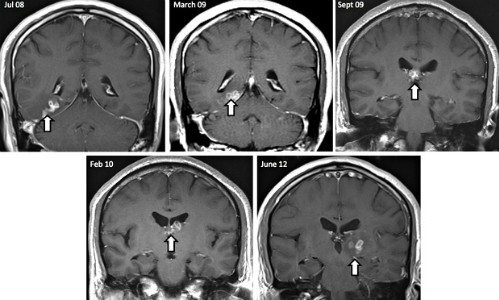

Năm 2013, các bác sĩ ở Anh phát hiện một dạng sán lạ di chuyển bên trong não bộ của một bệnh nhân. Sau nhiều lần chụp cắt lớp, họ phát hiện ra vật thể hình tròn kỳ lạ bên trong não của người đàn ông gốc Trung Quốc. Sán đã sống ký sinh trong đầu của ông trong 4 năm.

"Nó di chuyển từ nửa não bên này sang nửa não bên kia", bác sĩ Effrossyni Gkrania-Klotsas nói. Đây là dạng sán có thể di chuyển khắp cơ thể người như mắt, các mô hay phổ biến nhất là não.

Bệnh nhân từng quay về Trung Quốc trong thời gian gần đây. 4 năm trước đó, ông có những triệu chứng đầu tiên như đau đầu, nhưng được chữa trị như bệnh lao. Khi quay lại, người này có các triệu chứng mới, khi sán tấn công vào khu vực khác trong não bộ, gây co giật và đau ở chân. Các biểu hiện đều liên quan dạng sán dây hiếm gặp có tên khoa học là Spirometra erinaceieuropaei. Vì chưa có thuốc điều trị hiệu quả, các bác sĩ nhanh chóng phẫu thuật để loại bỏ chúng.

| Ảnh chụp scan cho thấy sự di chuyển của con sán trong đầu bệnh nhân qua thời gian (mũi tên). Ảnh: CNN |